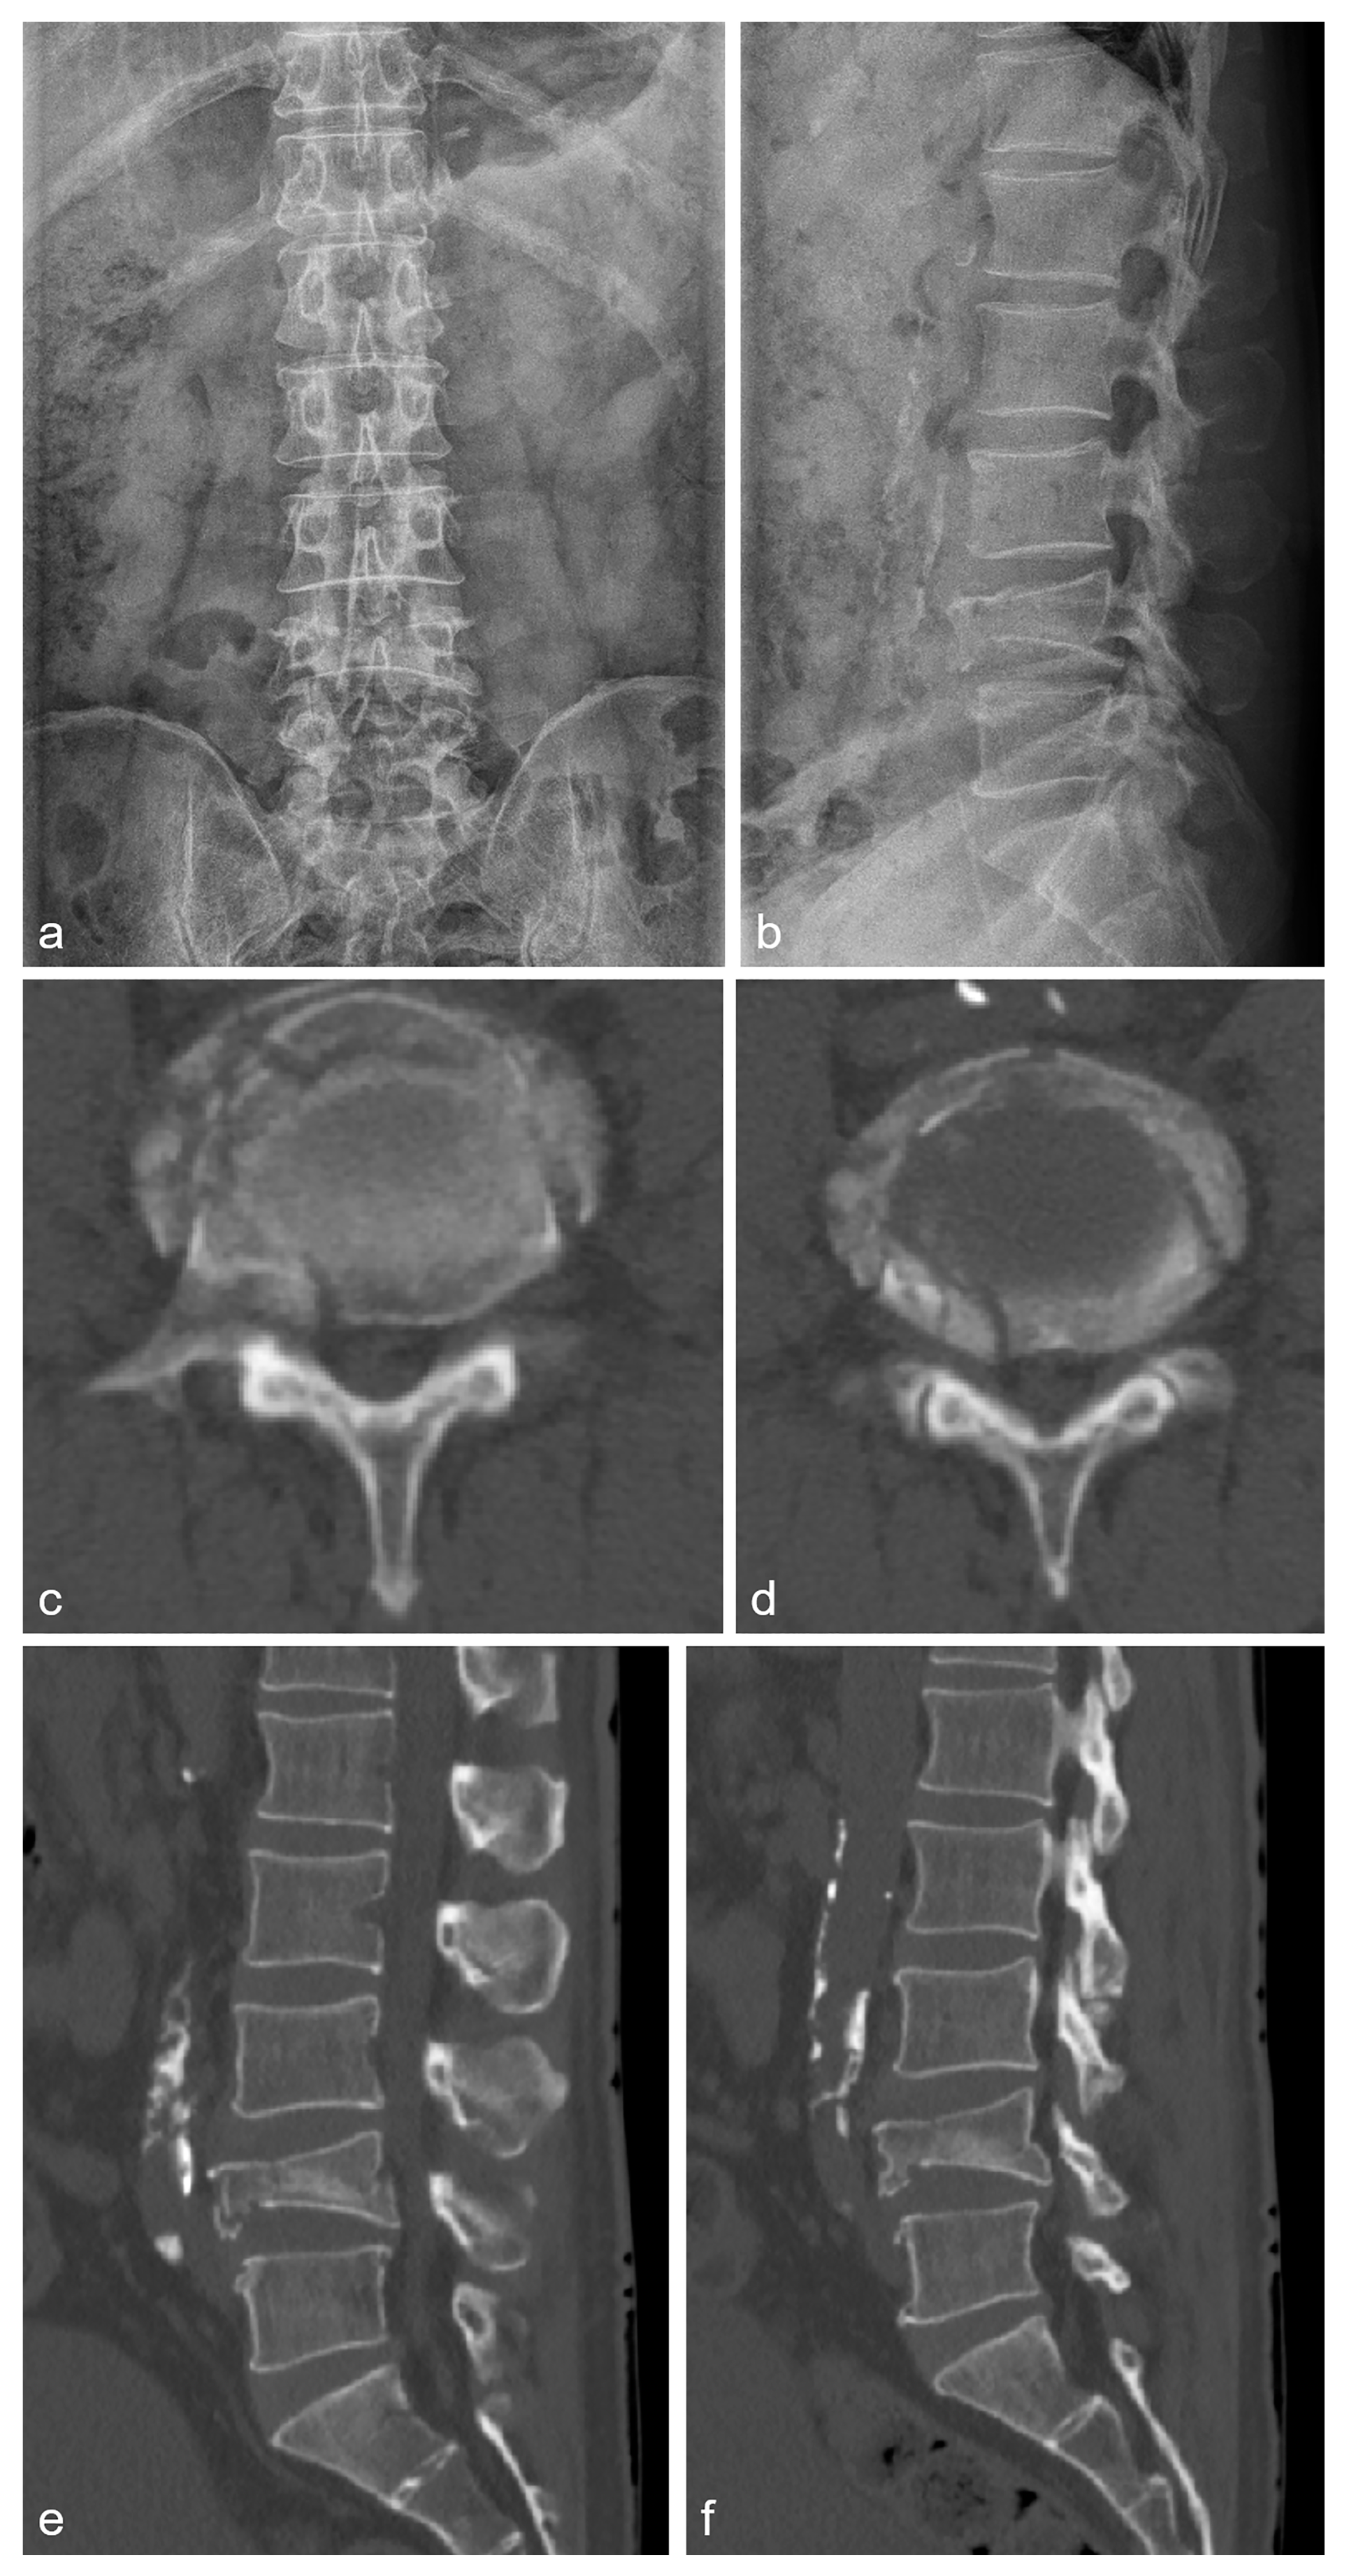

2.2. Case 2